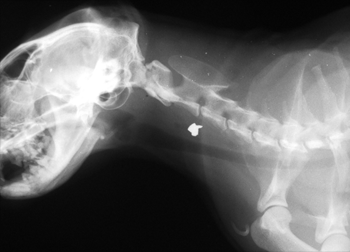

일반 X-Ray 촬영검사

흉부, 복부, 두부, 근골격계, 척추 촬영을 통해 환자 전반에 걸친 기본적인 정보를 획득할 수 있는 손쉬운 진단방법입니다. 본원 영상의학과의 X-선 검사장비는 디지털 검사장비를 도입하여 영상의 구현과 검사시간을 단축하였으며, 촬영시간은 물론 촬영 대기시간, 촬영에서 진단까지의 시간이 단축되어 환자 서비스 향상을 이룰 수 있습니다. 만일 촬영 후에 사진이 만족스럽지 않은 경우라 하더라도 촬영 후에 농도조정이 가능하기 때문에 불필요한 재촬영을 대폭 줄일 수 있습니다.